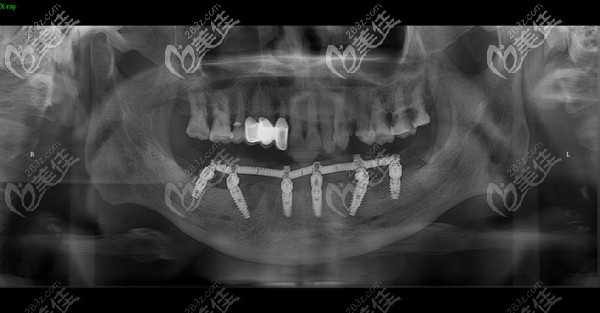

牙齒疾病或者是外在因素,都會導(dǎo)致牙齒缺失,那就需要做種植牙才能改善。一直聽說石家莊趙翠彩做即刻負重修復(fù)效果不錯,價格還不貴,來看下真實案例就知道。

鄭州口腔種牙還挺靠譜,1年前做的Allon6現(xiàn)在吃東西依舊輕松 b588 G0 V0

其實做種植牙不怕花的錢多錢少,就怕的是花錢買罪受,比如術(shù)后基臺和種植體的密合性不好,長期如此引起能發(fā)炎疼痛。所以一定要找一家口碑好的醫(yī)院做種植,就像鄭州金水區(qū)的口腔,